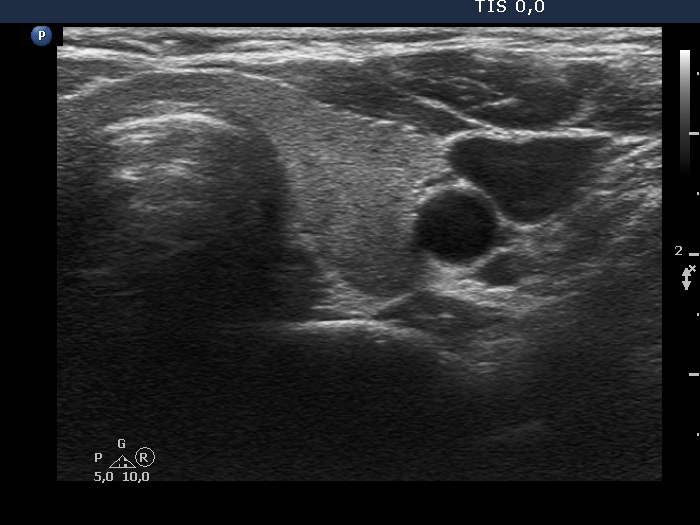

Clinical presentation: A 58-yr-old woman was referred for evaluation of a nodular goiter discovered on screening for 15 years. At the time of discovery, the largest diameter of the nodule was 10 mm.

Ultrasonography. The thyroid was echonormal. There was an echonormal nodule in the ventral part of the right lobe. The nodule showed halo sign but did not perinodular blodd flow.

1. It is worth noting that the nodule decreased the echogenicity of that part of the non-nodular part which was located dorsal to the lesion.

2. The nodule should be classified as an EU-TIRADS 3 lesion.